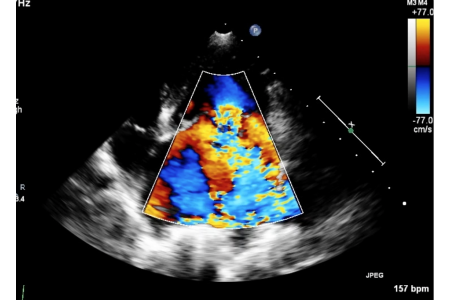

Objectives: To determine whether murmur intensity in small-breed dogs with myxomatous mitral valve disease reflects clinical and echocardiographic disease severity. Methods: Retrospective...